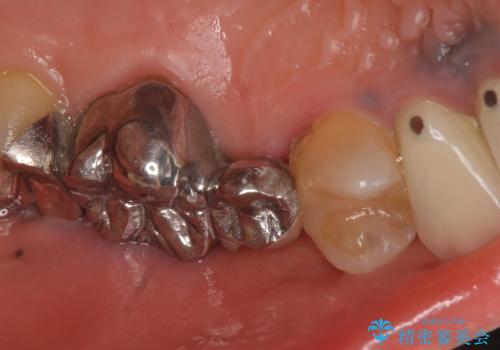

- 昔治療した左上56の延長ブリッジをきちんと治療しなおしたいといらっしゃった方の症例です。

古いブリッジを除去後、オールセラミッククラウンによる補綴を行いました。